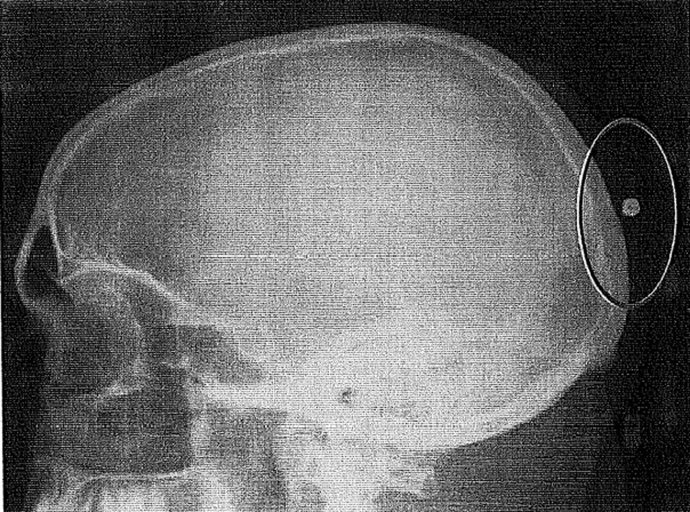

Radiografía del vigilante que recibió un perdigonazo en la cabeza

UN BALÍN EN LA CABEZA

Al llegar al punto donde debía fichar, una compañera le aviso de que tenía toda la chaqueta llena de sangre, con lo que se fue a un centro médico donde le extrajeron del cuero cabelludo lo que se comprobó que había sido un balín.